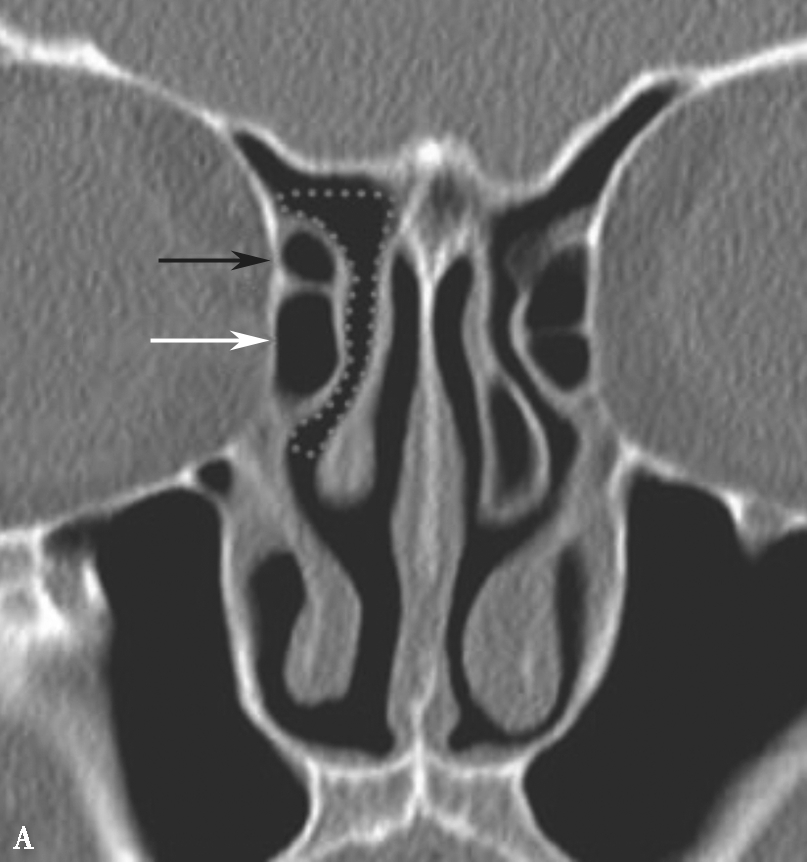

鼻丘气房位于筛漏斗的前上部,与泪骨、上颌骨、筛骨、额骨、鼻骨关系密切。是由筛漏斗直接发展而来。鼻丘气房通常位于额窦底的前部,构成额隐窝的前壁,大小不一,过大、过多可妨碍额窦引流,引起额窦炎。鼻丘气房和钩突眶内壁附着点之间的关系非常密切。当钩突与眶内壁没有附着点时,鼻丘气房不存在;当钩突与眶内壁仅有一个附着点时,鼻丘气房存在;当钩突与眶内壁有两个及以上附着点时,形成上下两个气房,在冠状面观察,偏下的气房称为鼻丘气房,偏上的气房称为额气房,两者内壁均由钩突构成(图1-3-1)。

图1-3-1 鼻丘气房及额气房CT解剖

A~C.鼻丘气房(五角星),额气房(星),钩突(白箭),筛骨纸板(箭头)

图1-3-5 筛漏斗解剖

A、B.额隐窝(虚线),鼻丘气房(白箭),额气房(黑箭)